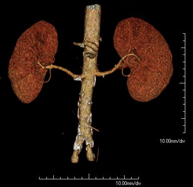

- Abdominal aorta CT angiography

A non-invasive diagnostic test that involves studying the abdominal aorta by obtaining high-definition anatomical images using CT (computed tomography) equipment and iodinated contrast. With the aid of workstations specialised for arterial studies, the image quality supports 2D and 3D reconstructions. It is indicated in patients with vascular disease (atherosclerosis), aortic aneurysms, abdominal pain of possible vascular origin, pre-surgical studies of lesions adjacent to the abdominal aorta as a vascular ‘map’, etc. Information obtained non-invasively is indispensable for patients requiring percutaneous or surgical processing. In patients who only require tracking of vascular lesions, this technique is the non-invasive technique of choice, together with MRI angiography.

- Renal artery CT angiography

A non-invasive diagnostic test that involves studying the renal arteries by obtaining high-definition anatomical images using CT (computed tomography) equipment and iodinated contrast. With the aid of workstations specialised for arterial studies, the image quality supports 2D and 3D reconstructions. This test is recommended, for example, in patients suffering from refractory hypertension that does not respond to processing, in patients with kidney damage in order to obtain a pre-surgical ‘vascular’ map, etc.

- Aortoiliac CT angiography

A non-invasive diagnostic test that involves examining the iliac arteries and abdominal aorta, obtaining high-definition anatomical images using CT (computed tomography) equipment and iodinated contrast dye. With the aid of workstations specialised for arterial studies, the image quality supports 2D and 3D reconstructions. This test is particularly recommended as a pre-surgical study (vascular map) prior to percutaneous or surgical interventions on the abdominal aorta, as a complementary study in patients with lower limb ischaemia, etc.